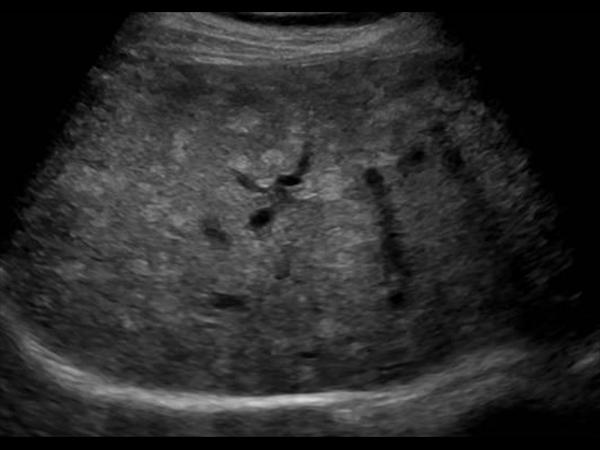

Gan nhiễm mỡ - Ảnh 3

Gan nhiễm mỡ

» Thông tin: Nữ giới – 59 tuổi.

» Lâm sàng: Kiểm tra sức khỏe.